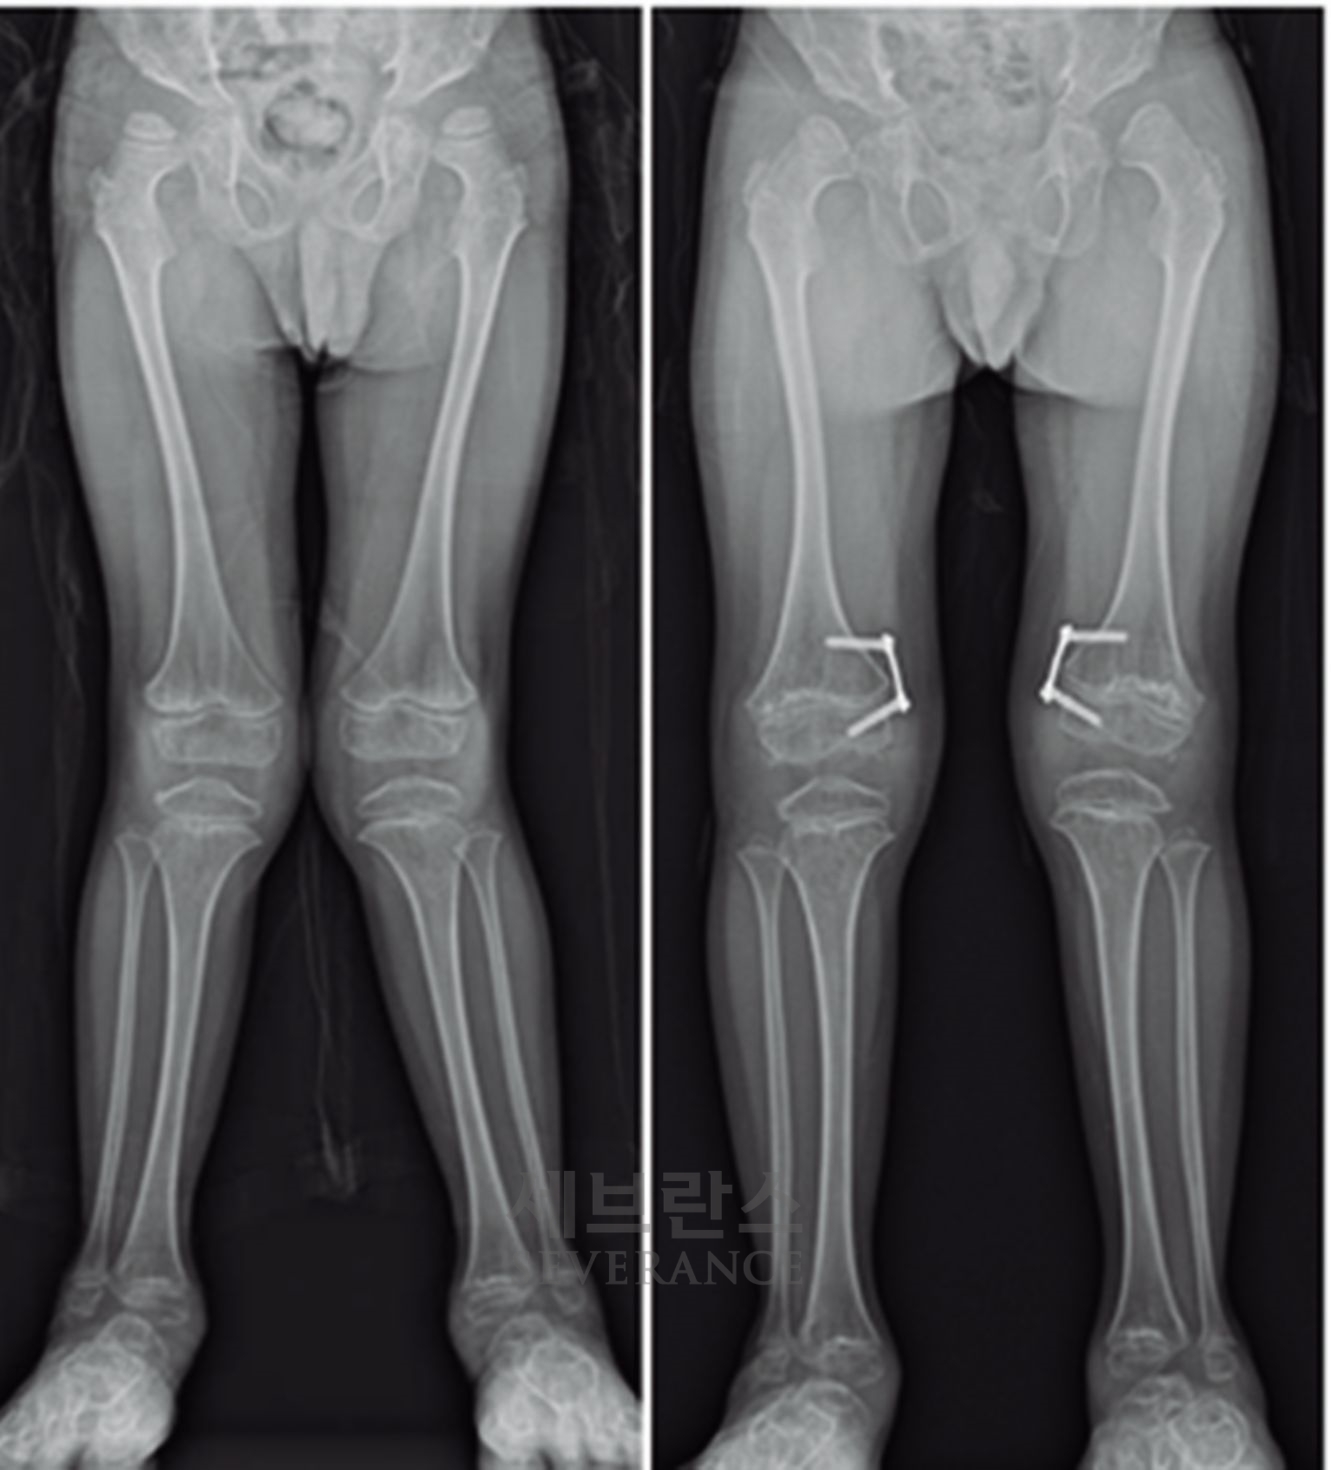

- 골연장술

양쪽 팔다리의 길이 차이가 큰 경우에 주로 시행하는 수술로, 외부 고정 장치나 내부 금속정을 이용해 뼈를 서서히 늘려 균형을 맞추는 방법입니다. 대체로 외부 고정 장치를 많이 사용하는데, 연장 기간 동안 날마다 정해진 횟수만큼 뼈를 조금씩 늘려야 하고, 핀 주변 소독도 꾸준히 해줘야 합니다. 연장된 뼈가 단단히 붙는 데도 수개월이 걸리기 때문에 환자와 보호자의 인내가 필요합니다.

성장판 손상으로 발생한 좌측 외반슬 및 하지부동에 대해 골연장술과 교정술을 동시에 시행해 치료한 환아